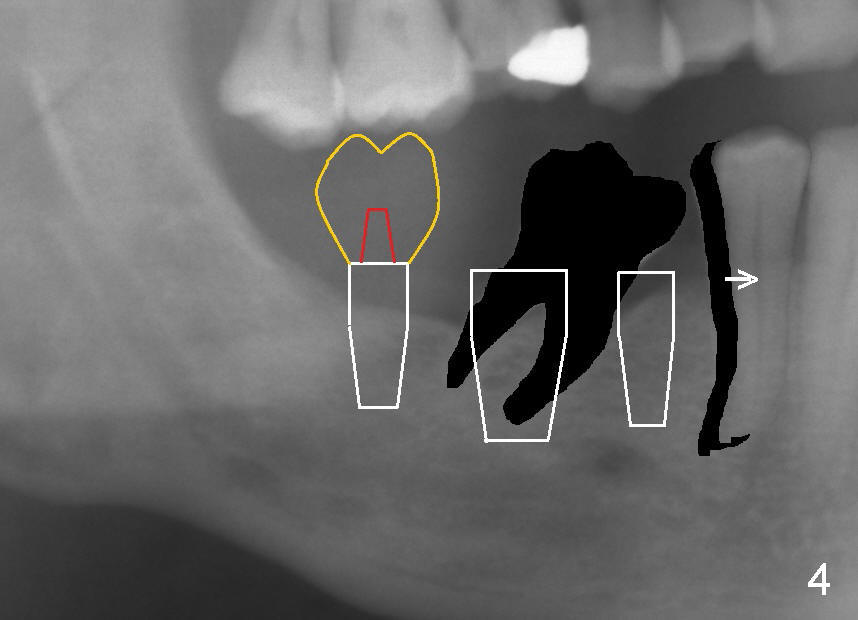

When the tooth #30 fails in the future, two more implants will be placed at the site of #29 and 30 after limited ortho moves the tooth #28 mesially (Fig.4 arrow).